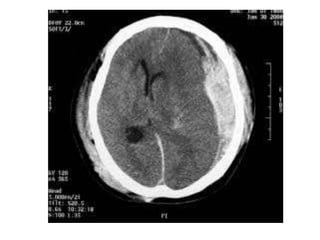

CT Brain

Case 1: 80yo F with fall • Fall in kitchen, L forehead laceration, confused, L shoulder pain • On warfarin for AF • How do you manage this patient?

• 11.

Primary Survey: • A- clear, Cx spine nontender ? Collar • B - equal AE bilat O2sats 96%RA RR 16 • C - HR 95 BP 140/80 no external bleeding • D - GCS 12 (M5 V4 E3) PEARL • E - T 35.5 • Management?

Management • Prevent SecondaryBrain Injury – Maintain cerebral perfusion (MAP – ICP) • Head 30° up • Maintain Normal BP/O2sats/CO2 • NeuroSurg Ref • Reverse Warfarin (MJA 2013) Clinical Setting Management – all w/h Warfarin INR >1.5 + life threatening bleeding Vit K 5-10mg, PTX 50 Units/kg, FFP 150-300mls INR >2.0 clinically significant bleeding Vit K 5-10mg, PTX 35-50 Units/kg INR > 4.5 + bleeding risk high Vit K 1-2mg PO or 0.5-1mg iv Any INR and minor bleeding risk Just W/H and recheck next day